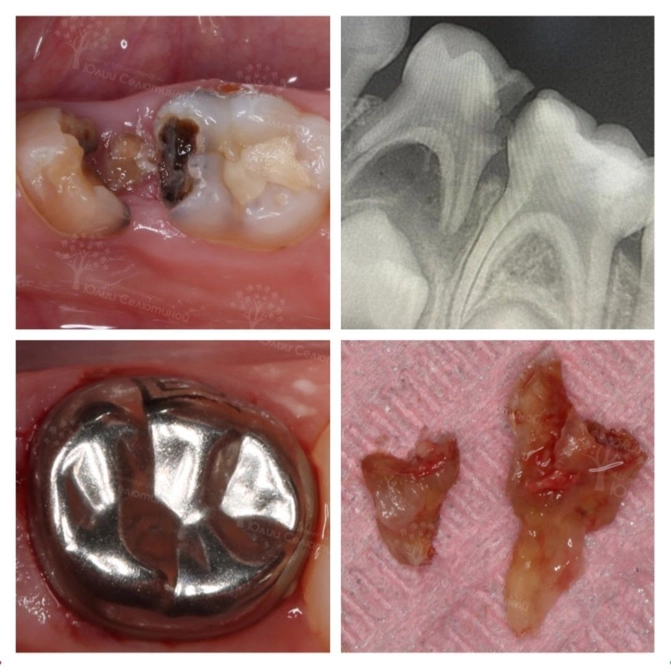

Что видим в полости рта?

"Четверка" сильно разрушена.

"Пятерка" тоже, но пока это только кариес.

По снимку нам очевидно, что "четверка" идет под удаление❌, т.к. разрушение большое и воспалительный процесс уже вышел за пределы зуба и угрожает зачатку постоянного.

"Пятерку" с кариесом лечим✔️

• И покрыли металлической коронкой;

• Ну а "четверку" удалили.